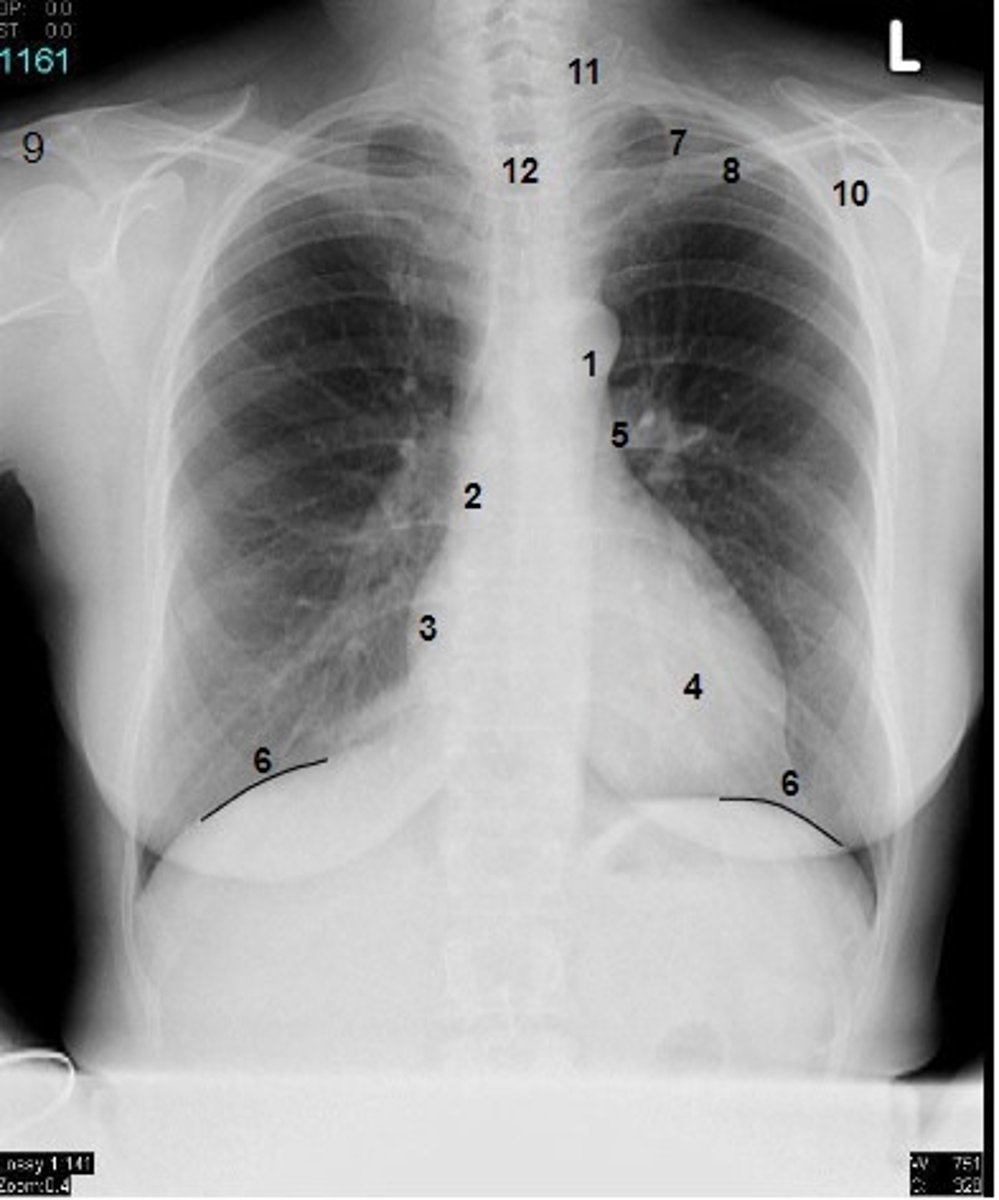

1

at what number is the arch of aorta?

2

at what number is the superior vena cava

3

at what number is the right atrium

4

at what number is the left ventricle

5

at what number is the primary bronchus

6

at what number is the dome of diaphragm

7

at what number is the first rib

8

at what number is the clavicle

9

at what number is the acromion of scapula

10

at what number is the coracoid process of scapula

11

at what number is the transverse process of vertebra

12

at what number is the spinous process of vertebra